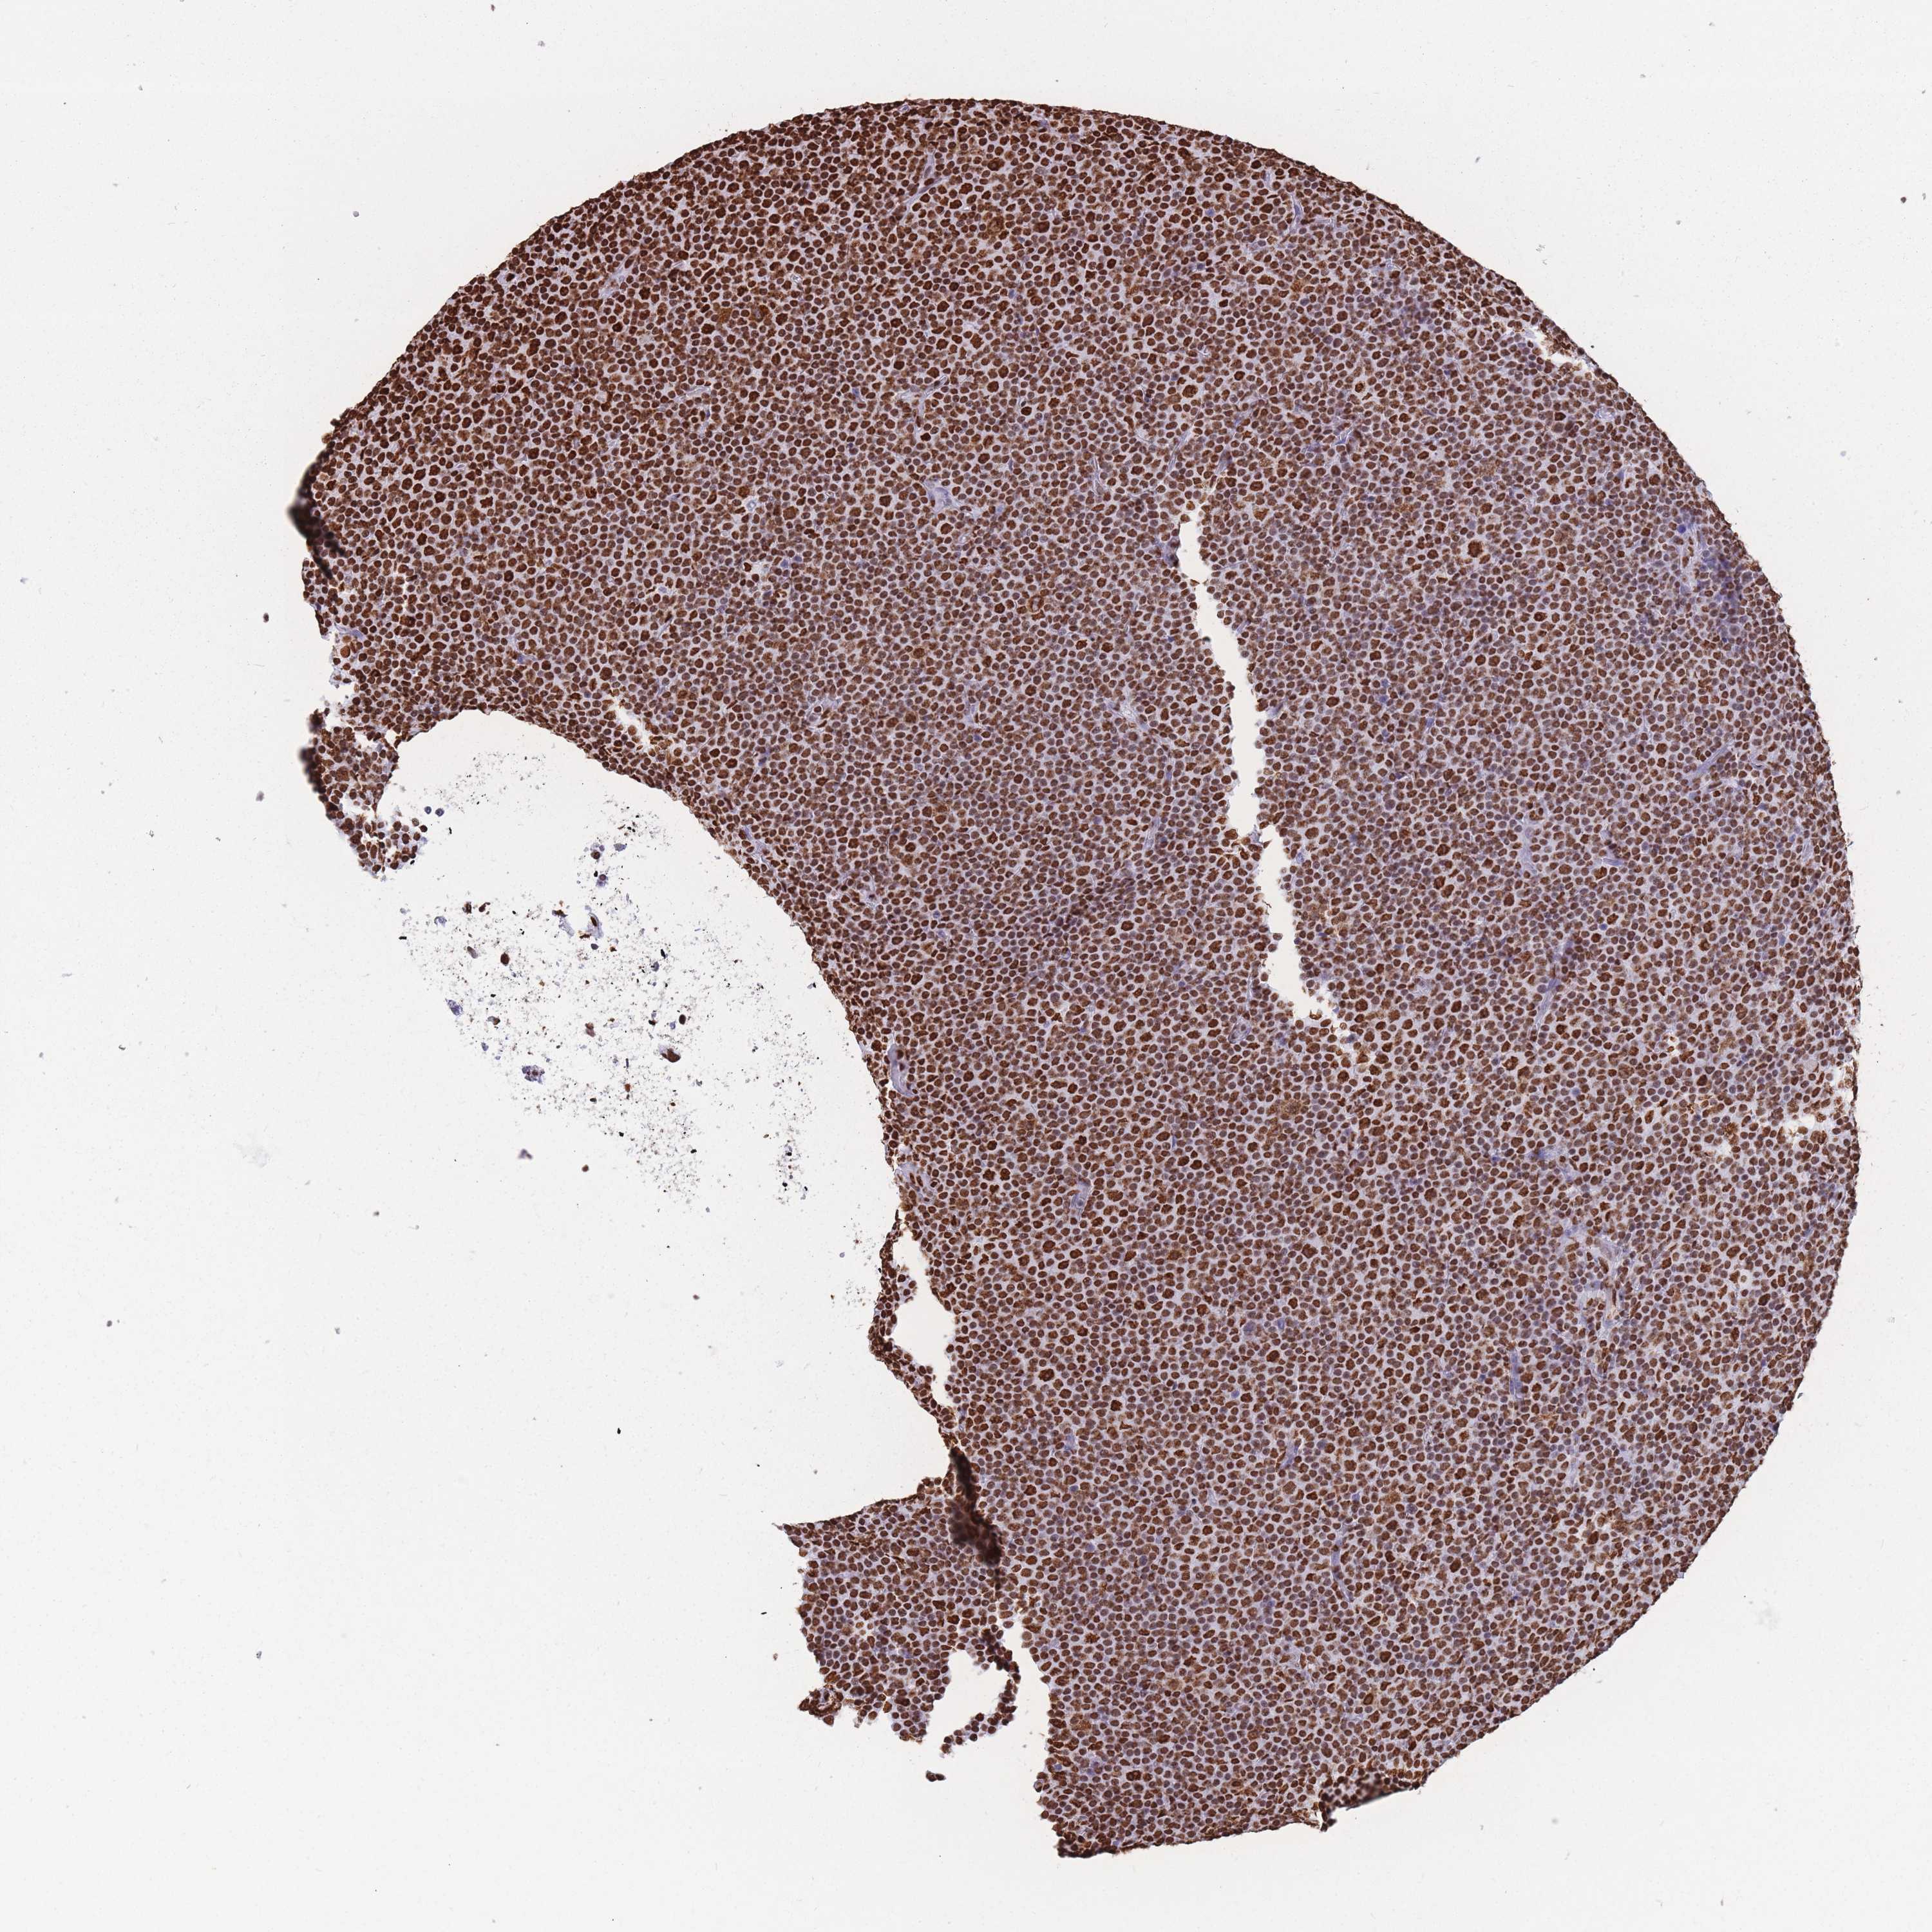

CANCER LYMPHOMA Show tissue menu

LYMPHOMA - Protein expressioni

A mouse-over function shows sample information and annotation data. Click on an image to view it in a full screen mode. Samples can be filtered based on level of antibody staining by selecting one or several of the following categories: high, medium, low and not detected. The assay and annotation is described here.

Each image is clickable and will lead to virtual microscopy that enables deeper exploration of all samples and also displays staining intensity scores, fraction scores and subcellular localization as well as patient and tissue information for each sample.

Antibody HPA046290

Antibody HPA049475

Antibody CAB046477

Hodgkin's disease, NOS

Malignant lymphoma, non-Hodgkin's type, High grade

Malignant lymphoma, non-Hodgkin's type, Low grade